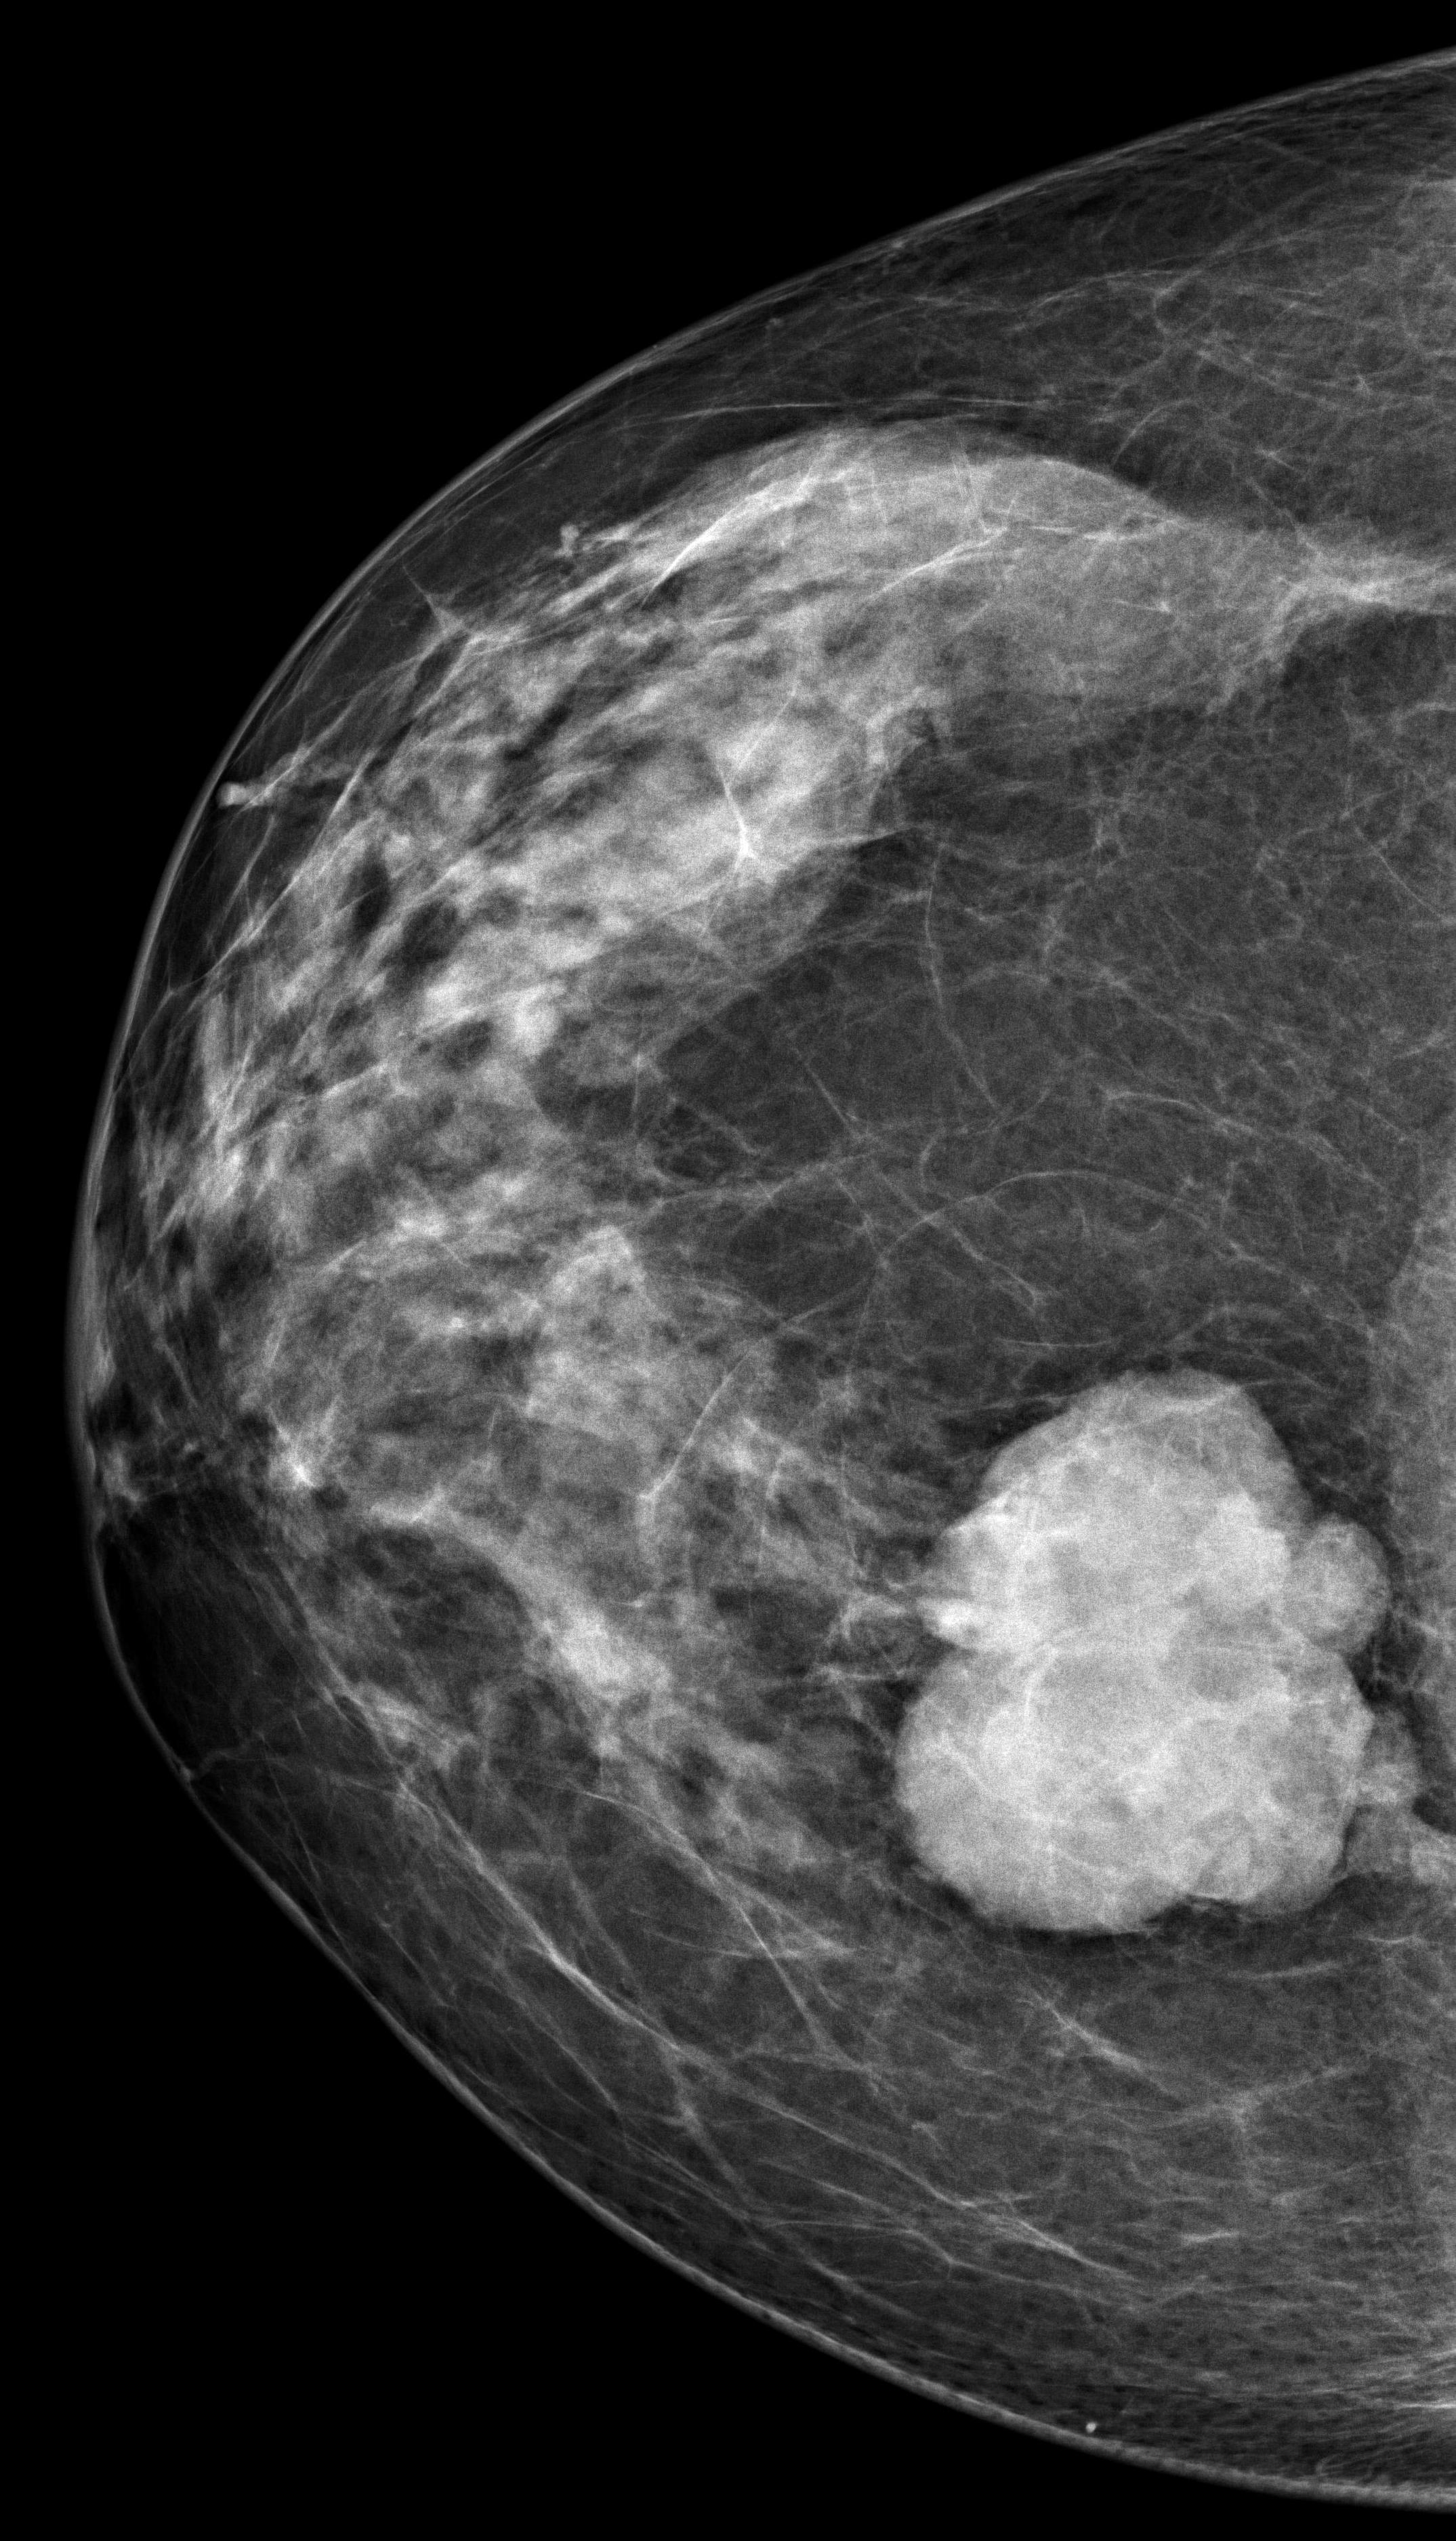

A 34-year-old woman presenting with a painless palpable right breast l...

Read More